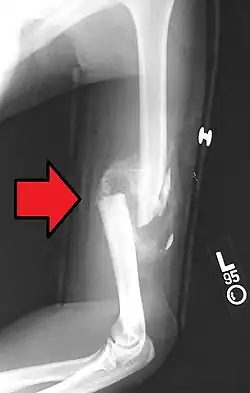

- Non-union: no progression of healing within six months of a fracture occurring. The fracture pieces remain separated and can be caused by infection and/or lack of blood supply (Ischaemia) to the bone.[9] There are two types of non-union, atrophic and hypertrophic. Hypertrophic involves the formation of excess callus leading to bone ends appearing sclerotic causing a radiological "Elephants Foot" appearance[6] due to excessive fracture ends mobility but adequate blood supply.[4] Atrophic non-union results in re-absorption and rounding of bone ends[6] due to inadequate blood supply and excessive mobility of the bone ends.[4]